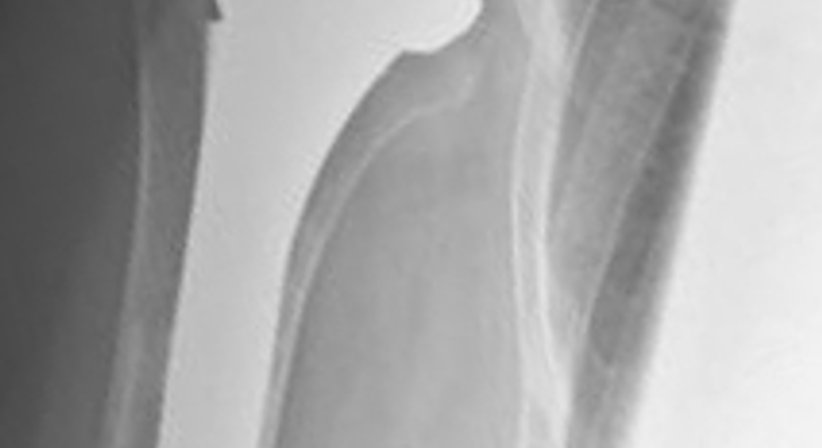

Seltener sind hochgradige Abnützungen des Schultergelenkes. Wenn diese mit Rissen an den Sehnen verbunden sind, so steht die Bewegungseinschränkung und der v.a. nächtliche Schmerz im Vordergrund. Auch hier kann Abhilfe geleistet werden, die sogenannte inverse Prothese (auch Grammont - oder DELTA Prothese genannt) ermöglicht es dem Patienten nach einem vergleichsweise kleinem Eingriff, die Schulter auch OHNE Sehnen wieder rasch und schmerzfrei bewegen zu können.